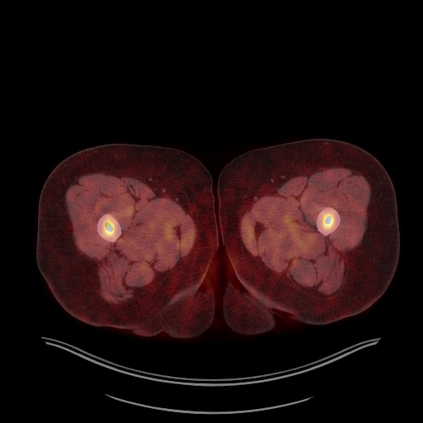

Medical images play a crucial role in assisting diagnosis, remote consultation, and academic research. However, during the transmission and sharing process, they face serious risks of copyright ownership and content tampering. Therefore, protecting medical images is of great importance. As an effective means of image copyright protection, zero-watermarking technology focuses on constructing watermarks without modifying the original carrier by extracting its stable features, which provides an ideal approach for protecting medical images. This paper aims to propose a fragile zero-watermarking model based on dual quaternion matrix decomposition, which utilizes the operational relationship between the standard part and the dual part of dual quaternions to correlate the original carrier image with the watermark image, and generates zero-watermarking information based on the characteristics of dual quaternion matrix decomposition, ultimately achieving copyright protection and content tampering detection for medical images.